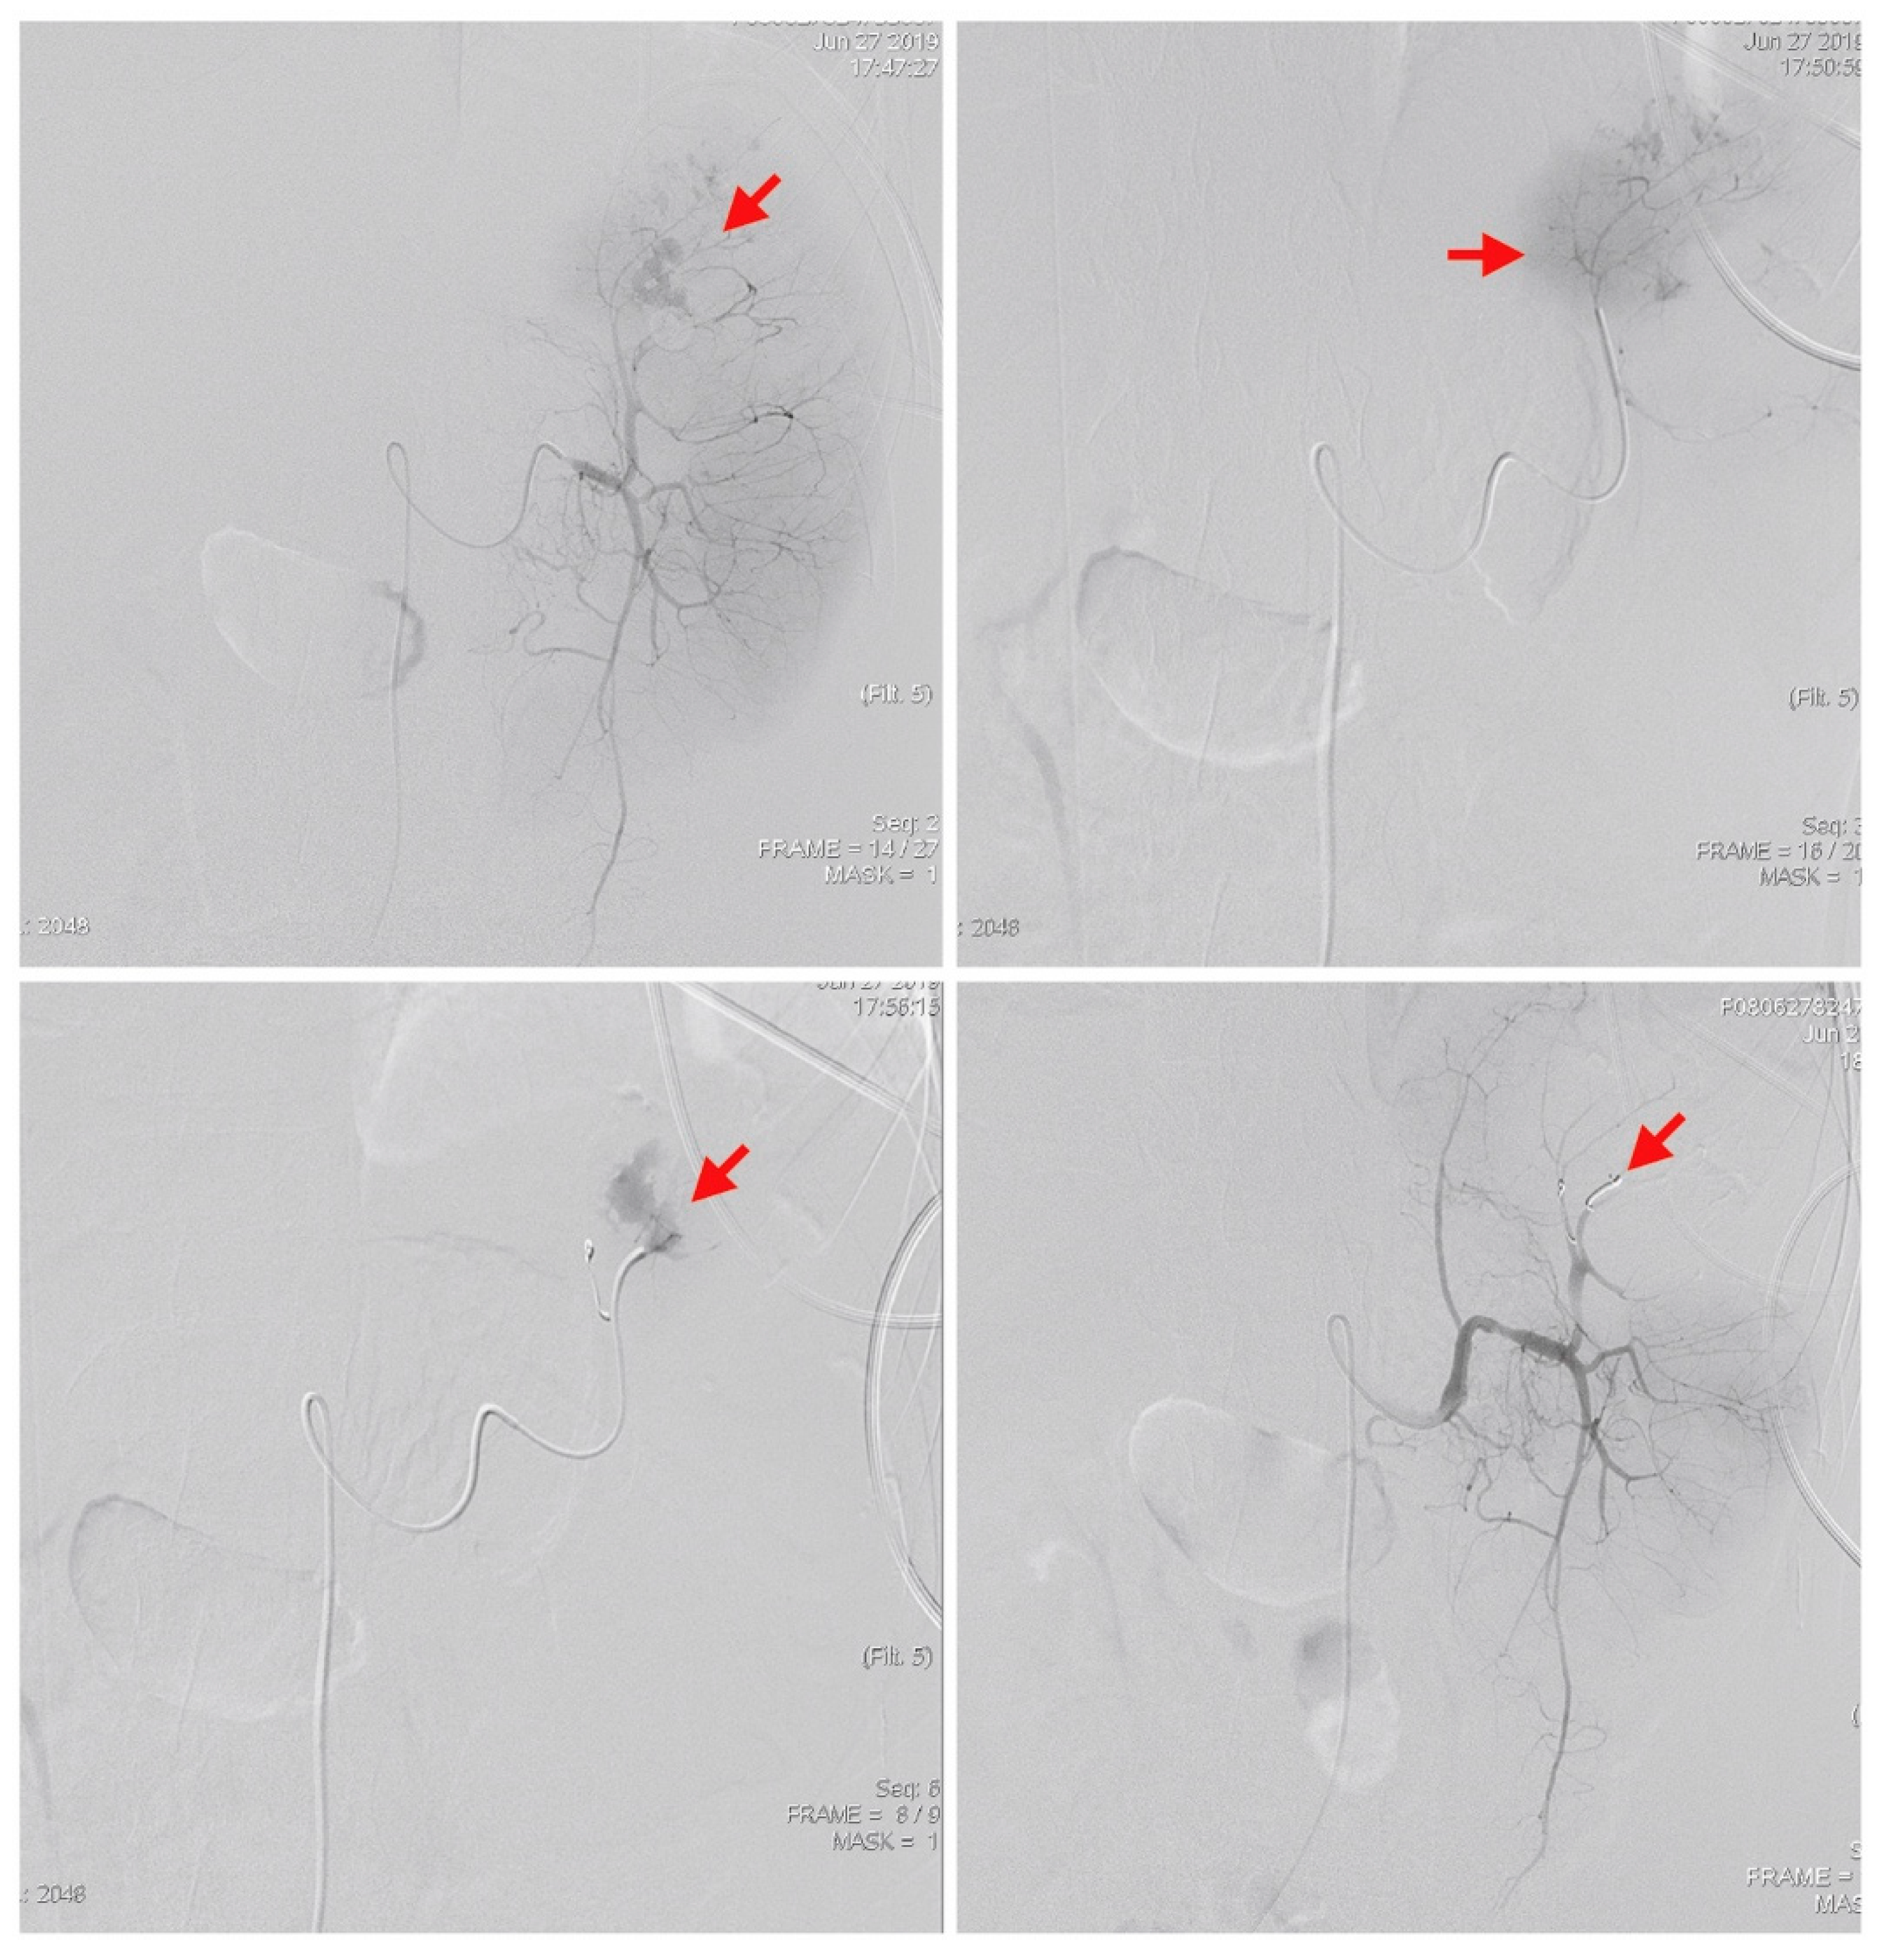

The bedside ultrasound revealed much ascites, which confirmed the emergency abdominal contrast enhanced computed tomography (CT) in the previous transfer hospital and showed splenomegaly and splenic rupture with hemoperitoneum (Figure 1). Adequate fluid resuscitation and emergency blood transfusion were performed to correct the hypovolemic shock status. Transamine (1000 mg) and vitamin K1 (10 mg) were administered to control the bleeding. The opioid agent morphine (10 mg) was used to control progressive abdominal pain. An emergency transcatheter arterial embolization was performed to control persistent splenic hemorrhage (Figure 2).

Figure 2.

An emergency transcatheter arterial embolization was performed using two coils to control splenic hemorrhage (red arrows).